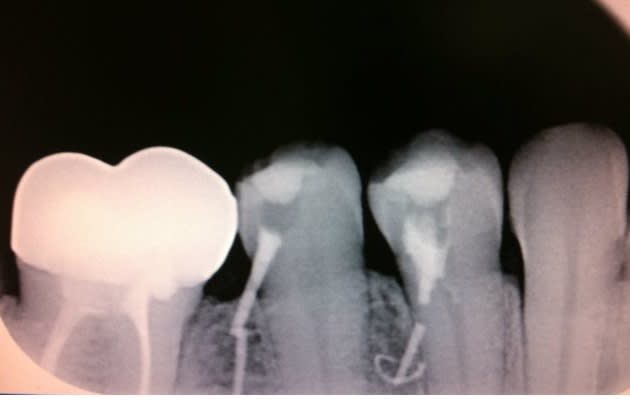

Ya des jours ou il ne faudrait pas aller au cabinet.. z'en pensez quoi?

je sais que j'ai légèrement dépassé sur la 45...

Greggy, les endos sont de toi? Si oui y'a effectivement souci.... mais on peut saluer ton courage.

Par contre belle constance dans le choix de l'axe, beau parallelisme!

ps: peut être un creneau pour ceux qui realisent des guides chirurgicaux, le guide d'endo ;0))